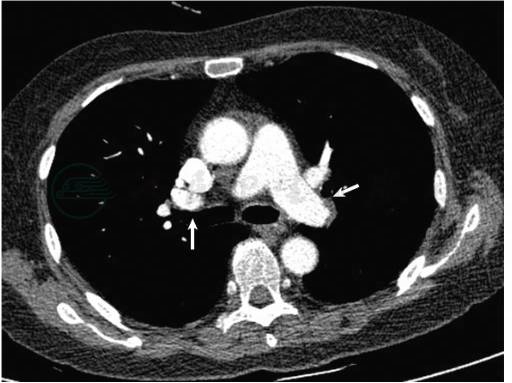

肺动脉CTA:右肺上叶动脉、中叶动脉、下叶动脉及其分支多发充盈缺损;左肺动脉主干末端、左肺上叶及下叶动脉及其分支多发充盈缺损(图1)。

图1 肺动脉CTA显示双侧肺动脉多发充盈缺损(白箭)